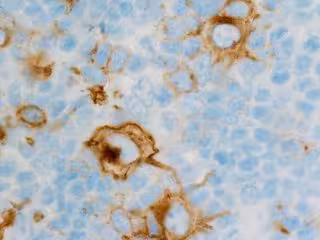

En el trabajo, que publica la revista 'Leukemia', los científicos han revelado la importancia de la proteína quinasa TAK1 en el diagnóstico de esta enfermedad rara, un subtipo de linfoma cutáneo de células T.

El estudio, en el que también han colaborado investigadores del IRB y del Idibaps, ha podido certificar, primero en modelos in vivo, en ratones y después con muestras de pacientes, que esta proteína, que ya se sabe que es esencial en el desarrollo de los linfomas de células B, está también activada en el Síndrome de Sézary.